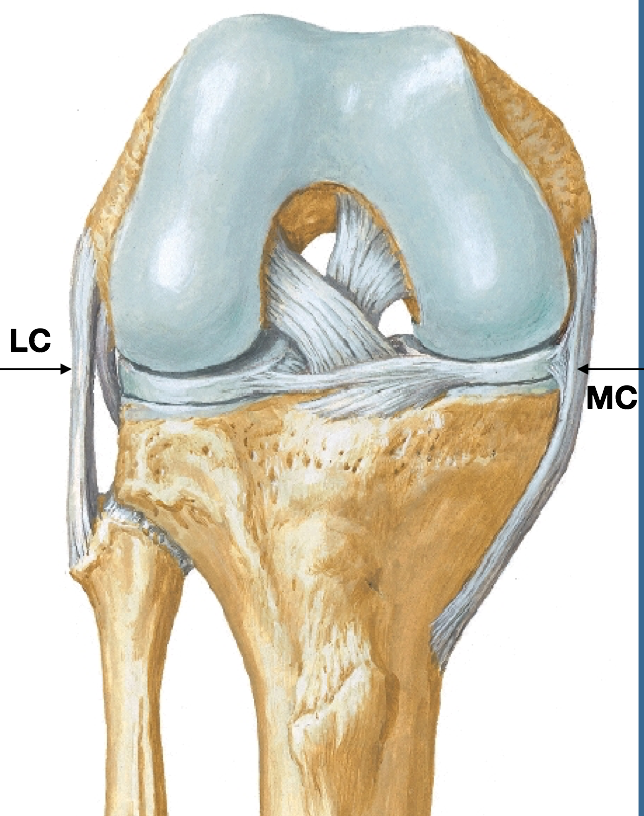

Extracapsular ligament support of the knee joint:

Lateral Collateral Ligament:

Medial collateral ligament:

Which collateral ligament of the knee is attached to a miniscus?

HIGH PROBABILITY OF MEDIAL MENISCUS TEAR WITH A MCL TEAR